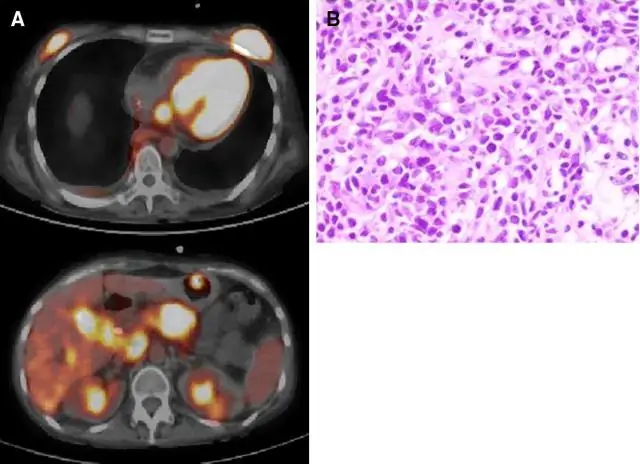

Команда Солка обнаружила, что Nup153 и Nup93 взаимодействуют с участками генома, называемыми суперэнхансерами, которые, как известно, помогают определить клеточную идентичность. Поскольку каждая клетка нашего тела имеет одинаковую ДНК, мышечную клетку отличает от клетки печени или нервной клетки то, какие конкретные гены включаются или экспрессируются в этой клетке. В исследовании Солка было обнаружено, что присутствие Nup153 и Nup93 регулирует экспрессию генов, управляемых суперэнхансерами, и эксперименты, которые подавляли любой белок, приводили к аномальной экспрессии генов в этих областях. Дальнейшие эксперименты на клеточной линии рака легкого подтвердили результаты линии рака кости: было обнаружено, что нуклеопорины в NPC взаимодействуют с несколькими участками суперэнхансеров, чтобы управлять экспрессией генов, в то время как эксперименты, которые изменяли белки NPC, приводили к нарушению экспрессии родственных генов, даже несмотря на то, что белки по-прежнему выполняли свою основную роль привратников в клеточной мембране.